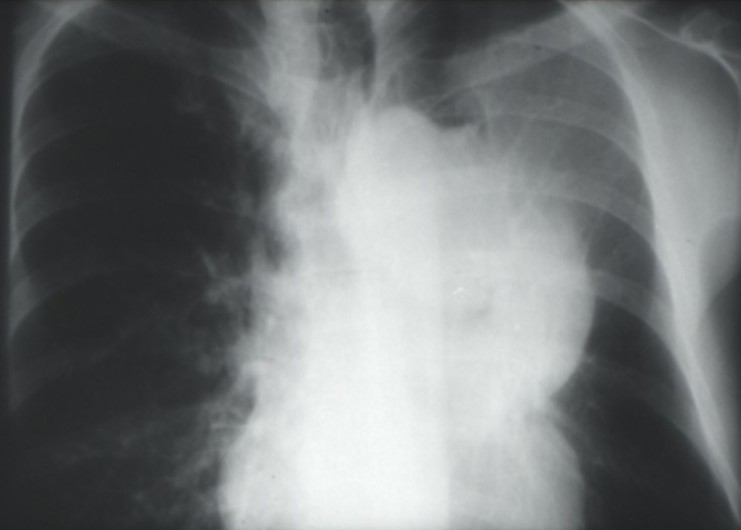

Cancers bronchiques